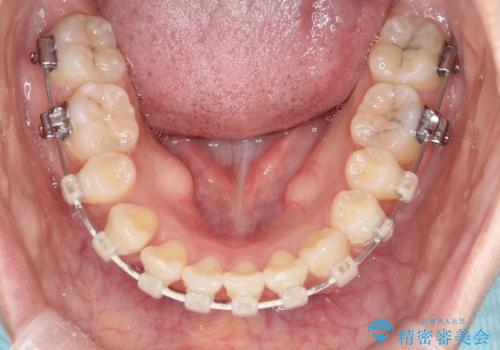

- 出っ歯、ガタツキ、噛み合わせが気になるとのことで来院された患者様です。

小臼歯を抜歯することでスペースを作り、前歯を下げて口元を下げ、Eラインを改善する治療方針としました。

表側のワイヤーは見た目が気になるとのことで、上の歯だけ裏側に付くハーフリンガルという装置で治療を行いました。